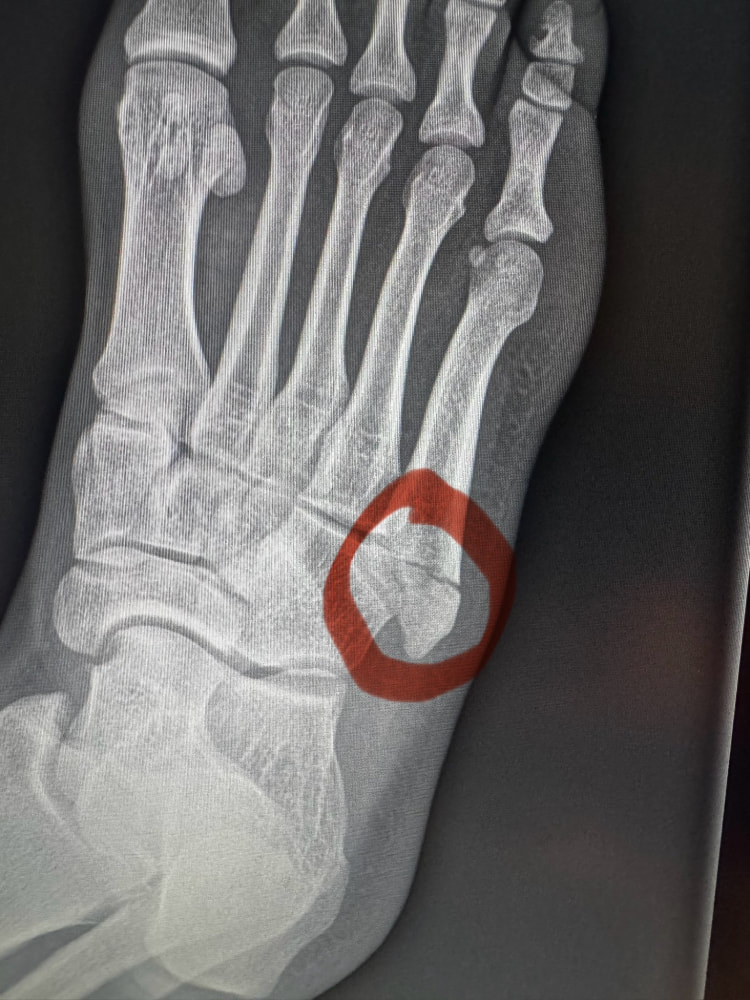

骨折した箇所を示すレントゲン写真@ManelKapeより